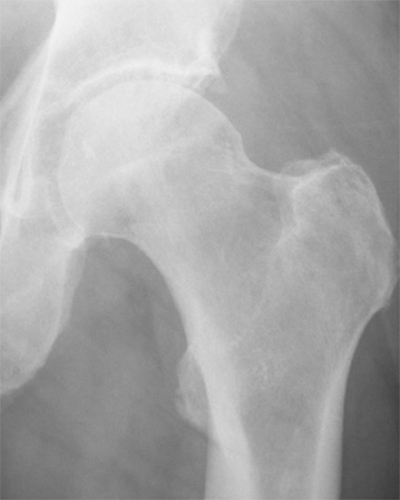

Coxarthrose

Die Arthrose ist eine Erkrankung des Gelenkes, bei der die knorpeltragende Schicht zunehmend dünner wird, bis in einem fortgeschrittenen Stadium ein unmittelbarer Knochenkontakt zwischen Hüftkopf und Pfanne besteht.